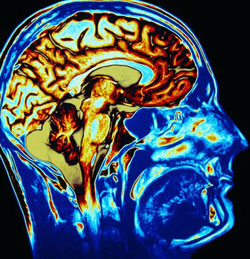

Creierul, un sistem care generează electricitate

În anii 1870-1880 medicul englez Richard Caton a fost primul care a descoperit faptul că creierul generează electricitate. Acesta a observat că la nivel cerebral se generează descărcări electrice mici. Caton a detectat de asemenea slabi curenţi electrici prin cutia craniană – cei care în prezent sunt înregistraţi cu ajutorul electroencefalografului. După trei decenii de la această descoperire, Santiago Ramon y Cajal, laureatul premiului Nobel pentru medicină şi fiziologie din 1906, a descoperit neuronul – unitatea structurală şi funcţională a sistemului nervos. El a observat şi modul în care neuronii îşi transmit impulsurile – prin legăturile sinaptice, realizând adevărate reţele „informaţionale”.

După încă 100 de ani, Roger Traub, de la Universitatea Birmingham din Anglia, a demonstrat că neuronii se conectează unul cu celălalt, nu numai prin sinapse, ci şi prin interacţiuni directe în câmp electric. Unul din misterele oscilaţiilor electrice de la nivelul creierului este modul în care ele se sincronizează pe zone întinse, într-un mod bine corelat, formând adevărate câmpuri electrice de intensitate scăzută, la nivel cerebral. Aşadar, neuronii de la nivelul creierului nu interacţionează doar fizic unii cu alţii, prin sinapse, ci şi direct, prin frecvenţe similare de vibraţie. Fiecare dintre aceste frecvenţe unitare de vibraţie, care înglobează activitatea neuronilor pe arii întinse, sunt generate de diferitele gânduri sau emoţii care apar la nivel psiho-mental.

Cercetătorii în neurologie au obiectivat reflectarea activităţii electrice a creierului, implicit a câmpurilor electrice care se generează la nivelul acestuia, în activitatea psihomentală şi reciproc. Înainte de această descoperire, psihofiziologii americani arătaseră că o reflectare similară are loc între activitatea psihomentală şi substanţele descărcate la nivel cerebral (neurotrasmiţători şi hormoni). Aşadar, activitatea electrică a creierului, cea chimică şi gândurile/emoţiile unei persoane sunt intercorelate. Aceeaşi informaţie este oglindită în diferitele structuri ale fiinţei umane.

În 1831, Michael Faraday a descoperit faptul că energia electrică în mişcare determină magnetism, iar mişcarea câmpului magnetic produce curent electric. Condiţia pentru transformarea energiei electromagnetice în energie electrică este ca „receptorul” să fie acordat pe aceeaşi frecvenţă de emisie a energiei electromagnetice. Activitatea creierului, fiind şi de natură electrică, poate fi influenţată, astfel de unde şi câmpuri electromagnetice. Undele radio, care şi ele aparţin spectrului electromagnetic, pot de asemenea produce curenţi electrici la nivel cerebral, dacă frecvenţa lor este similară celei cu care impulsurile nervoase sunt transferate între neuroni.